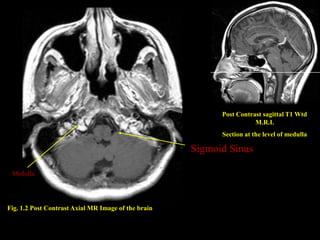

Post Contrast sagittal T1 Wtd

M.R.I.

Section at the level of medulla

Sigmoid Sinus

Medulla

Fig. 1.2 Post Contrast Axial MR Image of the brain

Post Contrast sagittalT1 Wtd M.R.I. Section at the level of medulla Sigmoid Sinus Medulla Fig. 1.2 Post Contrast Axial MR Image of the brain